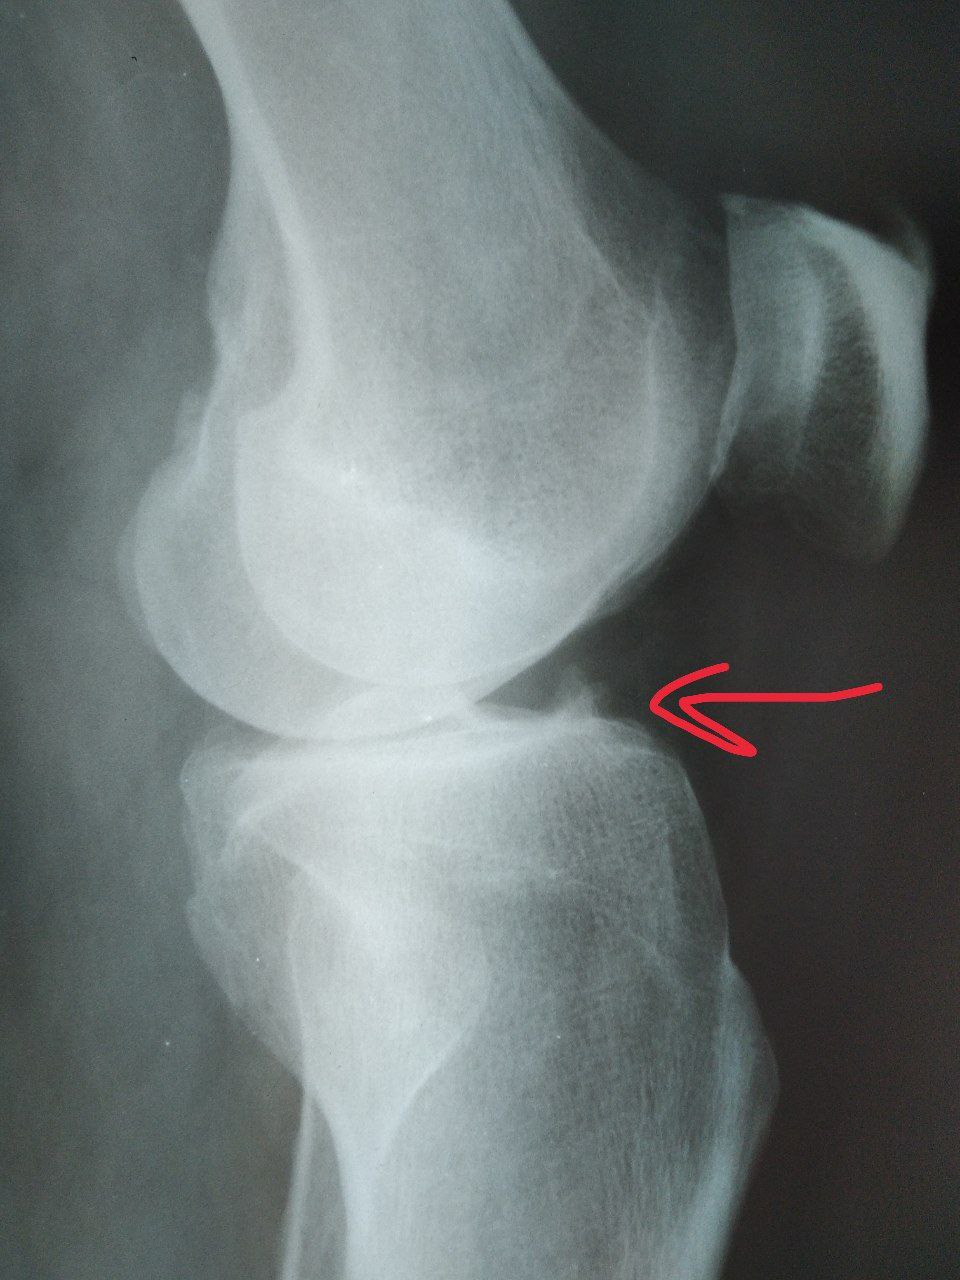

Оссификация ПКС в месте прикрепления к большеберцовой кости